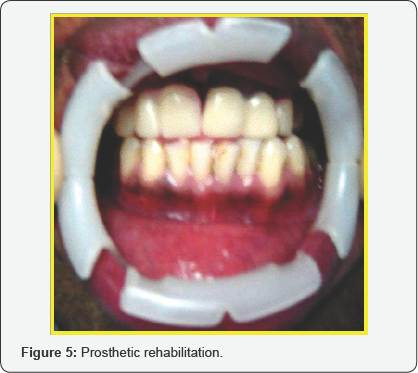

A 25 yrs old serving soldier reported to our center with severe mid facial injury due to Gun shot. On examination he was conscious, alert and oriented to time, place and person. His upper lip was torn in to two (degloving injury of the upper lip),nasal aperture shattered, dorsum was injured and his bridge of the nose was flattened (Figure 1). On intra oral examination there was avulsion of Upper anteriors on the right side and the left anteriors of the maxillary arch were fractured. Initially after stabilization the patient was subjected to CT scan and radiographs to rule out any injury to skull, brain and other bony injuries. After confirming there was no bony injury, a multidisciplinary approach was planned for comprehensive management. Patient was taken up under general anesthesia with oral intubation. Initially debridement was done and soft tissue closure was carried out in layers using 3-0 vicryl (Figure 2). The lip and nasal deformities were successfully corrected using a nasolabial flap. An inferiorly based nasolabial flap was designed. In this case the distal end of the flap is thinned by defatting and the distal part is folded and used as an inner lining. The inner layer sutured from proximal to distal by absorbable suture (4-O Vicryl) and the outer layer is sutured by (5-O Prolene). Care was taken to preserve the intervening skin bridge representing the nasofacial aesthetic line. To maintain the nasal patency and to retain the contour of the dorsum of the nose and nostrils, soft tissue closure was carried out with nasal stents placed inside the nostrils. Pressure dressing was placed and checked postoperatively. Sutures are removed after 5-7 days postoperatively. The right maxillary anteriors, tooth no 11, 12 and 13 which were fractured, avulsed and beyond restorable were extracted (Figure 3). The fractured teeth no 21 and 22 were root canal treated (Figure 4), core build up was done and porcelain fused to metal crown was placed. The missing teeth on the right maxillary arch which were extracted were prosthetically restored by using removable acrylic partial denture (Figure 5). There were multiple surgeries carried out by the Plastic surgery department. The patient underwent successive surgeries to get the final and better soft tissue shape and characteristic for both nostrils. Follow up was done for a period of one year and there were no post-operative or rehabilitative complications (Figure 6).